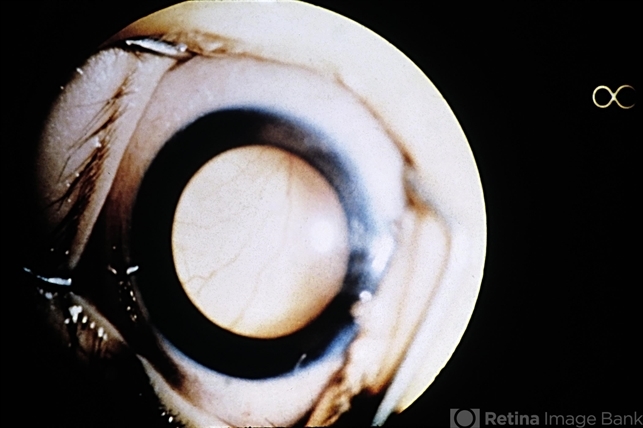

- leukocoria, retinoblastoma

- Characteristic leukocoria (white pupil) of retinoblastoma.